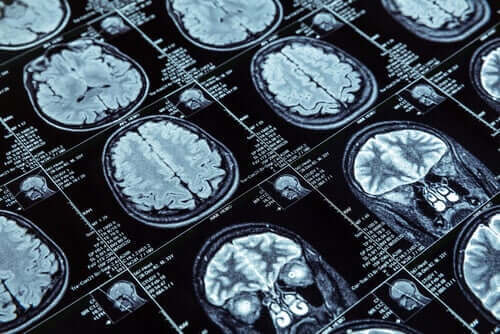

For at udføre denne forskning, lavede de MR-scanninger på mere end 600 personer, der var 45 år gamle. Disse 600 personer er en del af en større enhed, der består af mere end 1000 personer. I New Zealand har de studeret dem siden barndommen.

De målte tykkelsen af hjernebarken og mængden af grå masse gennem MR-scanninger, som de udførte på forsøgspersonerne. Disse data gav mulighed for en sammenligning mellem dem, der udviste antisocial adfærd, og dem, der ikke gjorde.

MR-scanningerne af hjernen hos disse personer viste en krympning af hjernebarken, når den blev sammenlignet med andre. Derudover, havde de en til dels mindre mængde grå masse.